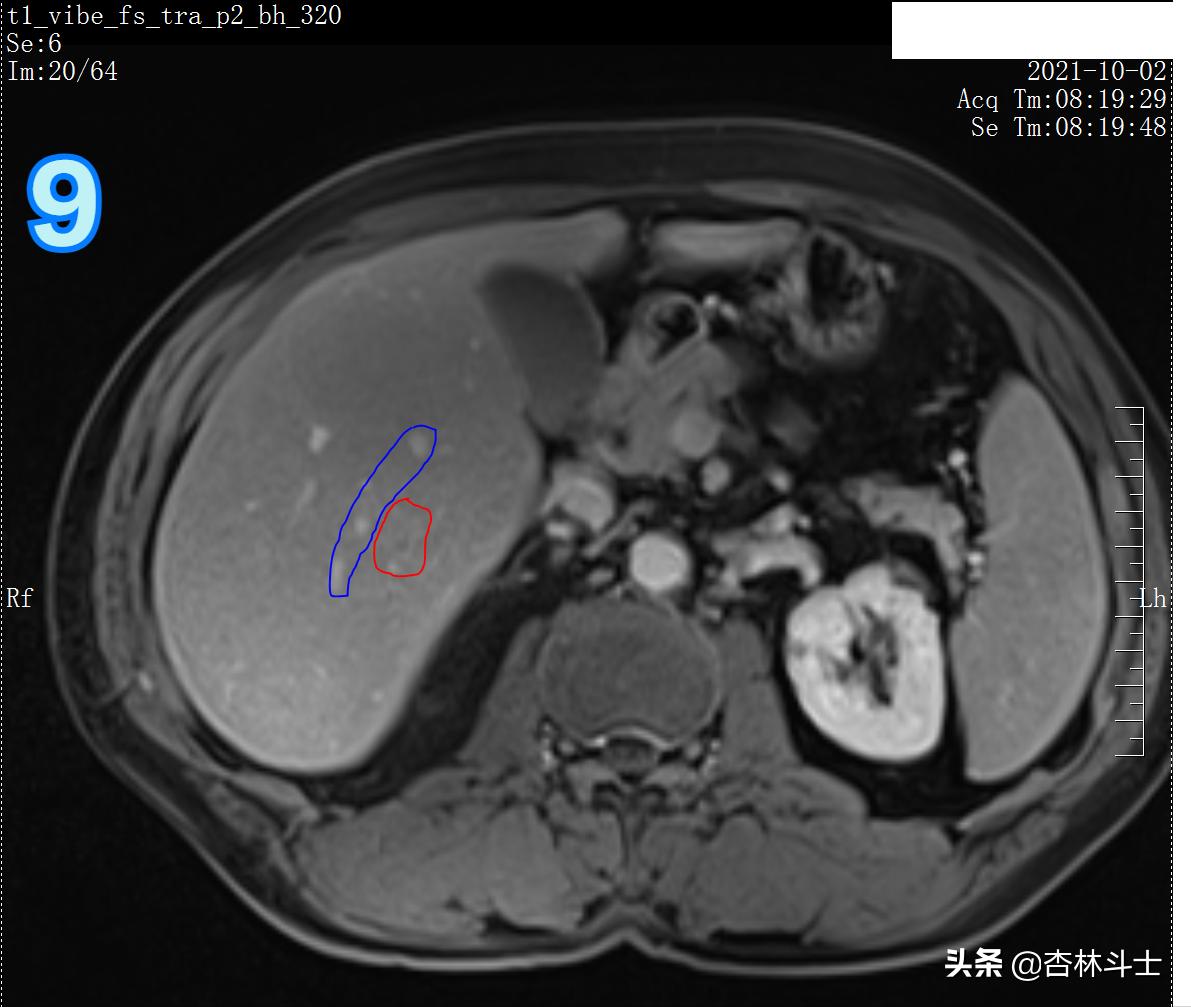

T1加权压脂

图9 蓝框为血管 红框为病灶,病灶在门静脉期呈等略低信号。蓝框血管目的为方便定位新发病灶。